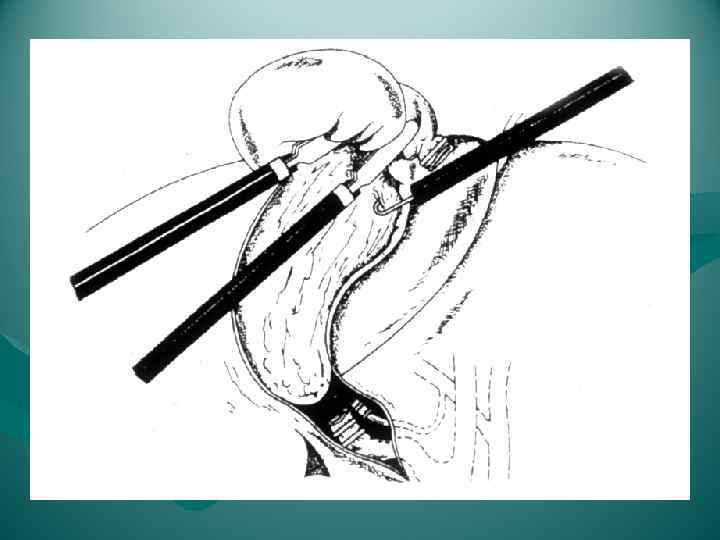

Перевязка левой печеночной вены.

Перевязка левой печеночной вены.